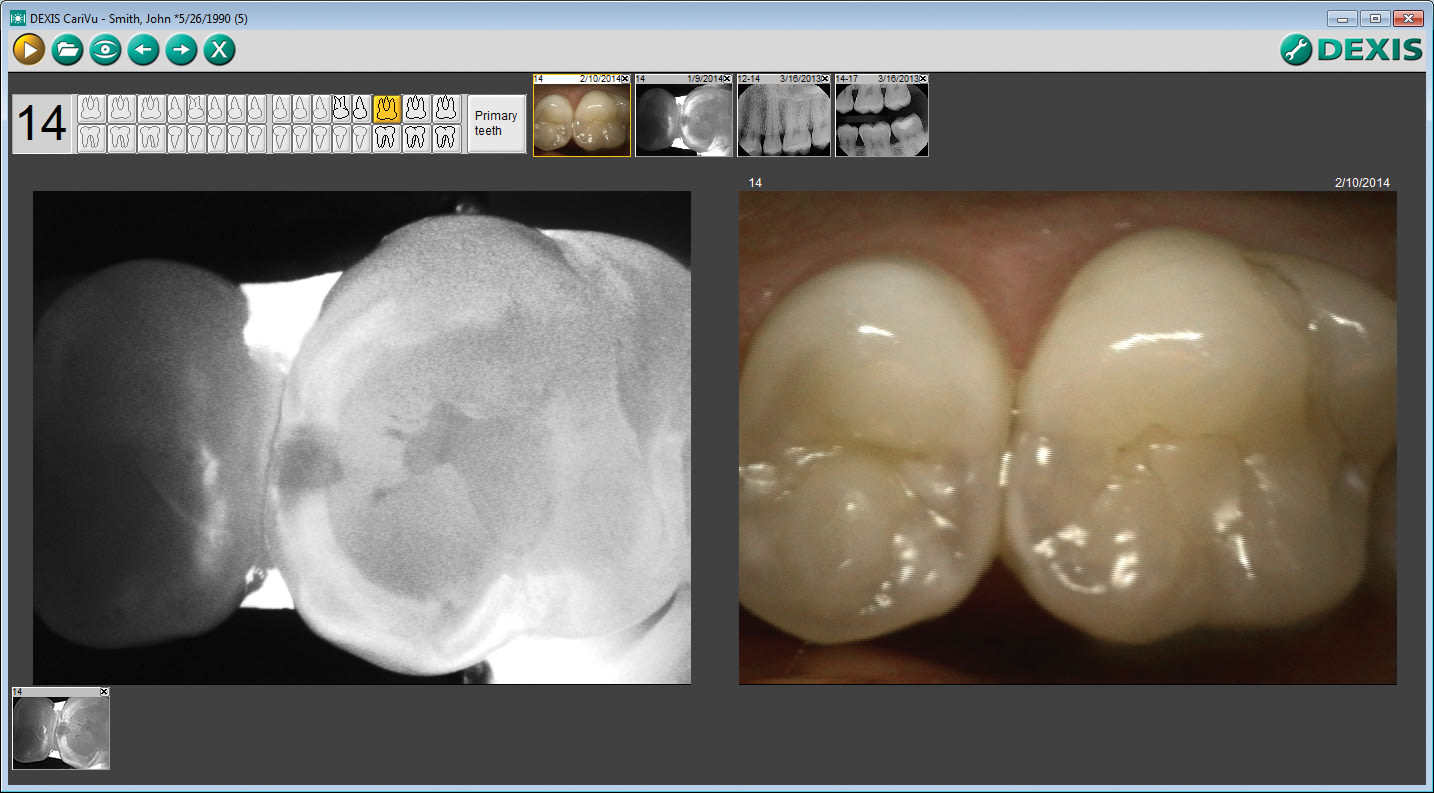

While many new technologies interest me, the CariVu caries detection device (Figure 1) has become a perfect addition to my imaging tools. This device uses near-infrared (NIR) light that illuminates both sides of the tooth simultaneously to detect carious lesions and cracks interproximally, occlusally, and around cracks and restorations. CariVu’s technology is different than other types of caries detection devices—some show results through a range of colors or a number that correlates to a degree of mineralization. On a CariVu image (Figure 2), healthy parts of the tooth appear light and lesions appear dark because healthy structures reflect the NIR light, whereas the porous carious lesions trap and absorb the light.

The CariVu device yields an understandable image without the need to clean the tooth of bacteria, calibrate the device, or become versed in the meaning of multiple color codes or numeric indicators. The NIR technology eliminates these extra steps, making caries detection that much faster and simpler for the clinician and the patient.

This technology has helped me with diagnosis and patient education, and is easy to use. A rubberized tip hugs the tooth to illuminate it from the buccal and lingual aspects for the capture of a clear picture. I can easily move the tip around, pivot it for an active visualization of the field, and change the focal depth as I move across the tooth to get a better 3-dimensional concept of the tooth. After I transilluminate the patient’s tooth, I can capture the image and enlarge it as necessary to show the patient areas of concern.

Even patients who are not receptive to low-dose digital x-rays can benefit because CariVu technology does not involve radiation. While it does not eliminate the need for x-rays, CariVu is a helpful addition to other imaging technologies, in some cases changing my expectations. With this device, I know the exact location and extent of the decay before opening the tooth. Sometimes for various reasons, x-rays have been misleading. I have opened teeth that I thought might have significant caries around a fracture and found little to none, and I have found teeth where I expected little decay around a fracture that had substantial caries.

According to a research study, CariVu technology has an interproximal dentin caries detection rate of 99%.1 This accuracy gives me a sense of security because I know the size and scope of decay and the extent of fractures that I would not have otherwise seen on an x-ray. Therefore, I am better prepared to excavate and restore the space. Being able to see the correlated size, shape, and scope of initial carious lesions, as well as around margins of failing restorations, lets me effectively plan treatment and allows for smaller accesses and less invasive treatment.